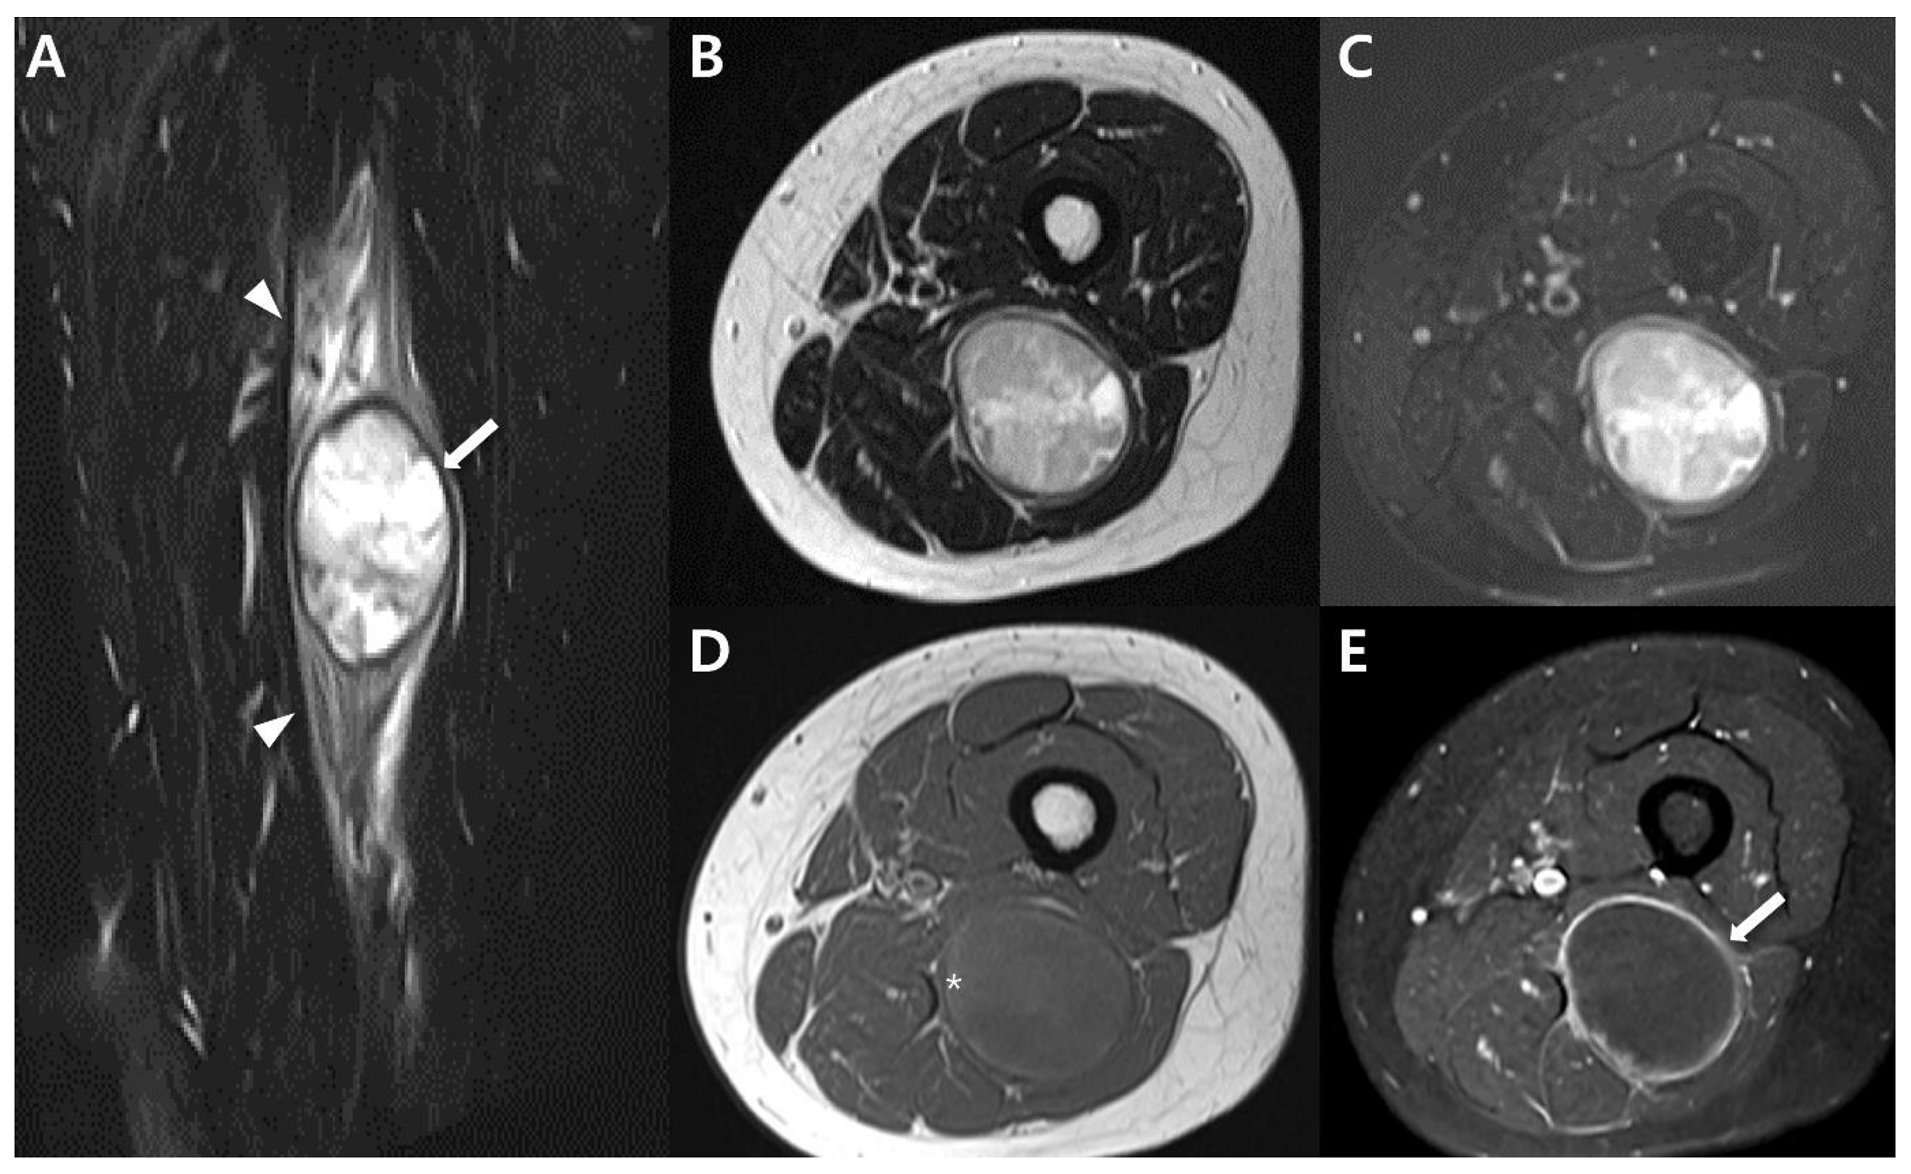

2.4. Magnetic Resonance Imaging (MRI)

2.5. Advanced MRI

3. Uncommon Primary Sites of Synovial Sarcoma in the Extremities

| Imaging features | Intratumoral hemorrhage (fluid-fluid levels) | Poor |

| Triple sign on MRI | ||